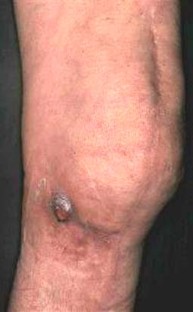

Abb. 2